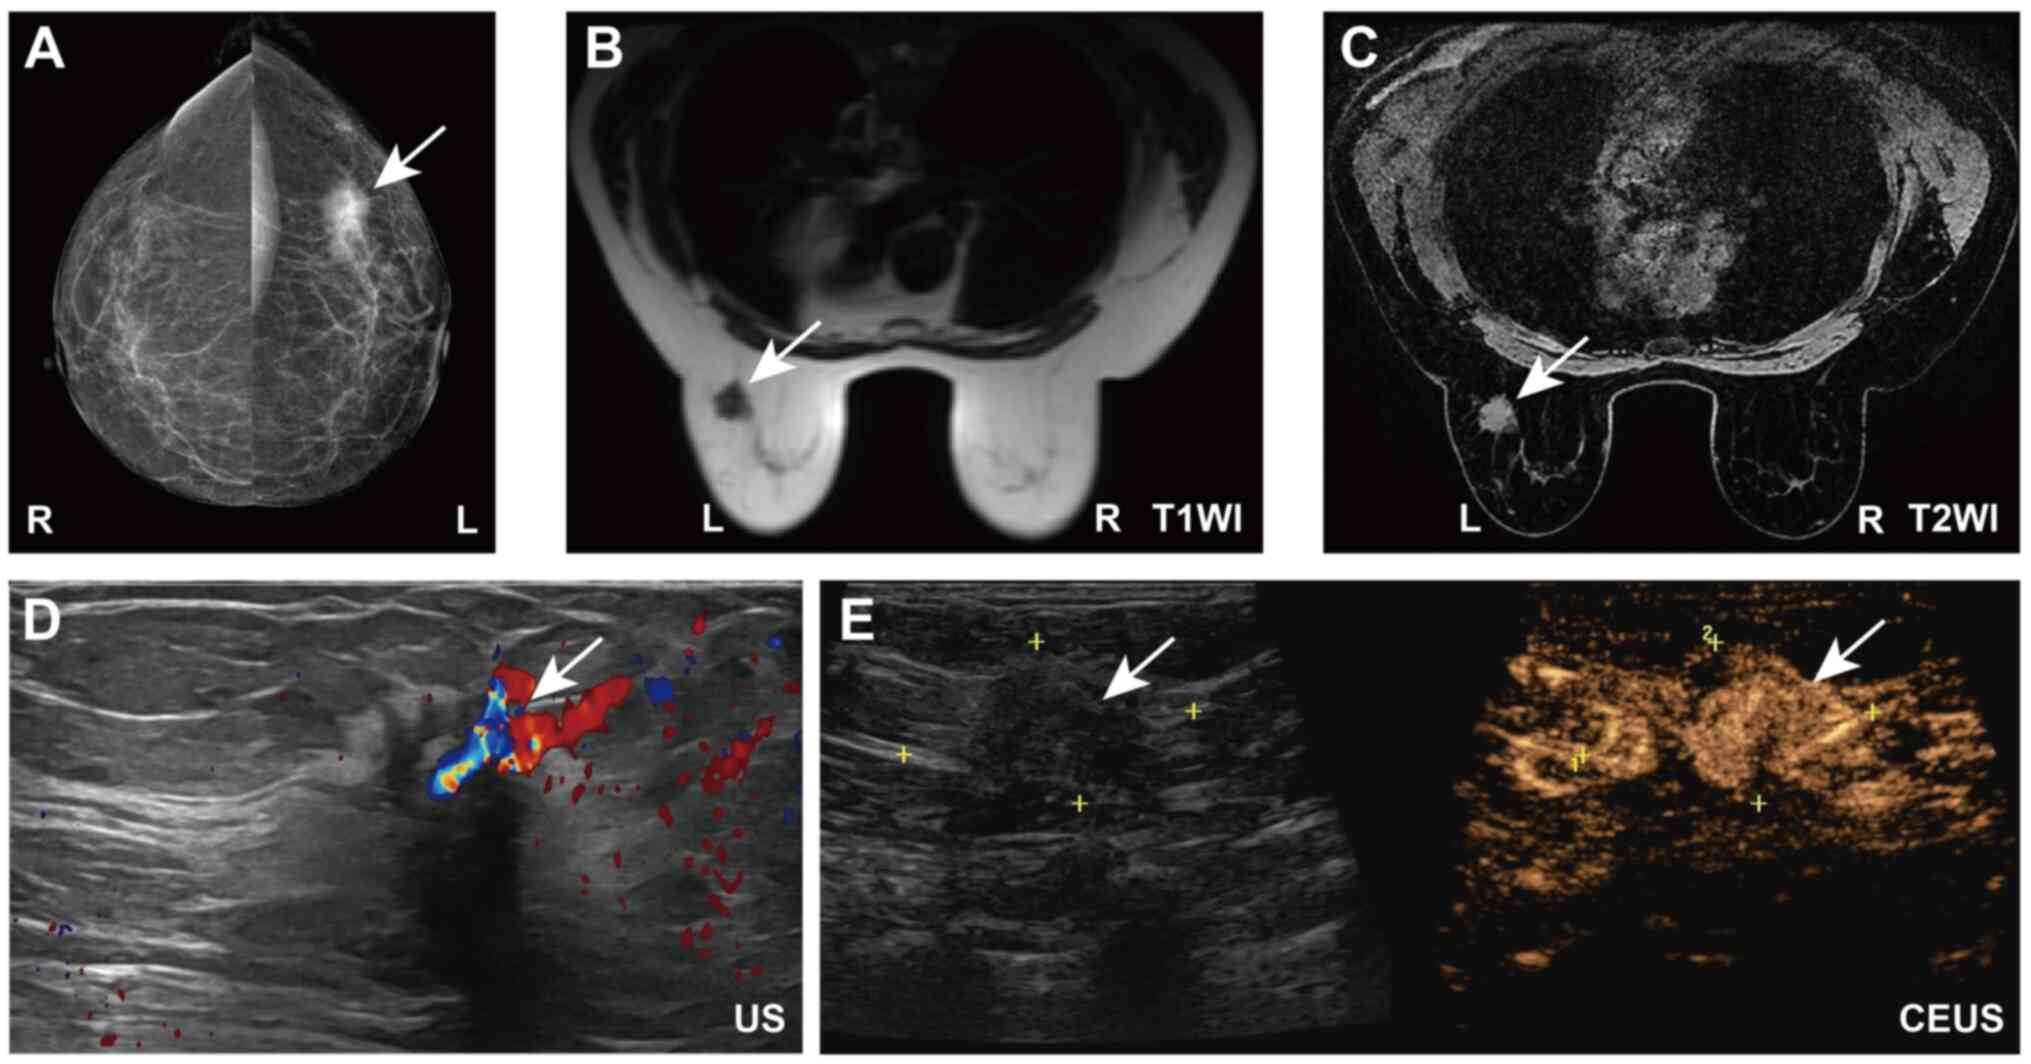

A 54-year-old woman was admitted to The Third People's Hospital of Chengdu (Chengdu, China) in November 2024. The patient had noticed a lump in the left breast >6 months prior to admission, but delayed seeking medical care due to the absence of symptoms such as pain, skin irritation or nipple discharge. Upon admission, a comprehensive physical examination performed by the attending physician revealed a hard, poorly mobile mass measuring ~2 cm in diameter, which was palpated in the upper outer quadrant of the left breast. The mass was mildly adherent to the surrounding tissues. No significant lymphadenopathy was detected in the axilla or supraclavicular region. In addition, routine physical examinations of the cardiovascular, respiratory and abdominal systems revealed no abnormalities. The patient had no notable past medical history. Mammography revealed a high-density, irregularly shaped mass measuring ~35×24 mm with spiculated margins and internal calcifications in the upper outer quadrant of the left breast (Fig. 1A). Moreover, MRI of the breast indicated a mass of ~20×18 mm in the upper outer quadrant of the left breast, with an irregular shape and spiculated margins. The lesion demonstrated low signal intensity on T1-weighted images, along with mixed signals on fat-saturated T2-weighted images and notable enhancement on contrast-enhanced images (Fig. 1B and C). Additionally, color Doppler breast ultrasound demonstrated a hypoechoic nodule measuring ~20×14 mm at the 2–3 o'clock position of the left breast and 4 cm from the papilla (Fig. 1D). After contrast injection, the lesion, measuring 35×17 mm in size, exhibited uneven high enhancement and prominent vascular structures (Fig. 1E). A core needle biopsy indicated invasive breast cancer in the left breast (Fig. S1A and B). Immunohistochemistry (IHC) results revealed that the biopsy sample cells were positive (30%) for Ki-67 (exceeding the 14% threshold), strongly positive (90%) for estrogen receptor (ER), moderately-to-strongly positive (30%) for progesterone receptor (PR) and negative (1+) for human epidermal growth factor receptor 2 (HER2) (Fig. S1C-F). The interpretation of the IHC results was based on the 2024 Guidelines of the Chinese Society of Clinical Oncology (CSCO) for Breast Cancer (7). Specifically, ER and PR were considered positive if ≥1% of tumor cell nuclei showed staining; HER2 expression was interpreted according to standard scoring criteria, with 0–1+ regarded as negative, 2+ as equivocal (requiring fluorescence in situ hybridization confirmation) and 3+ as positive; and Ki-67 was considered high if the proliferation index was ≥14%. Additional preoperative examinations, including chest and abdominal computed tomography (CT), cranial CT and a whole-body bone scan, demonstrated no evidence of distant metastasis or abnormalities. Serum tumor marker levels were also assessed and demonstrated to be within normal ranges: Carcinoembryonic antigen (CEA) was 2.64 ng/ml (reference value, <4.7 ng/ml) and cancer antigen 15-3 (CA15-3) was 18.9 U/ml (reference value, <26.2 U/ml). The initial diagnosis was left-sided breast cancer (luminal B type, cT2N0M0, stage IIA) (7,8). The tumor measured >2 cm in diameter, with no clinically evident axillary lymph node involvement and no signs of distant metastasis, consistent with a clinical stage of IIA (cT2N0M0) (8). According to these findings, as well as the results of the immunohistochemical analysis, the tumor was classified as the luminal B molecular subtype (7).

Preoperative imaging data of the

patient. (A) Mammography. (B) T1- and (C) T2-weighted breast

magnetic resonance imaging. (D) Actually color-Doppler ultrasound

and (E) contrast-enhanced breast ultrasound of the patient before

surgical treatment. White arrows indicate the location of the

tumor. CEUS, contrast-enhanced ultrasound; WI, weight imaging.

Figure 1.

Preoperative imaging data of the patient. (A) Mammography. (B) T1- and (C) T2-weighted breast magnetic resonance imaging. (D) Actually color-Doppler ultrasound and (E) contrast-enhanced breast ultrasound of the patient before surgical treatment. White arrows indicate the location of the tumor. CEUS, contrast-enhanced ultrasound; WI, weight imaging.